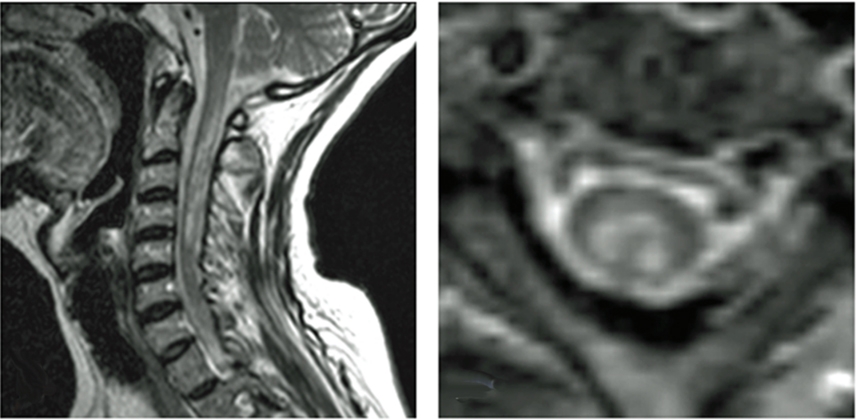

NMOSD MOG Ab Disease Sarcoidosis Paraneoplastic Dural AVF Cord Infarction Cervical Spondylosis